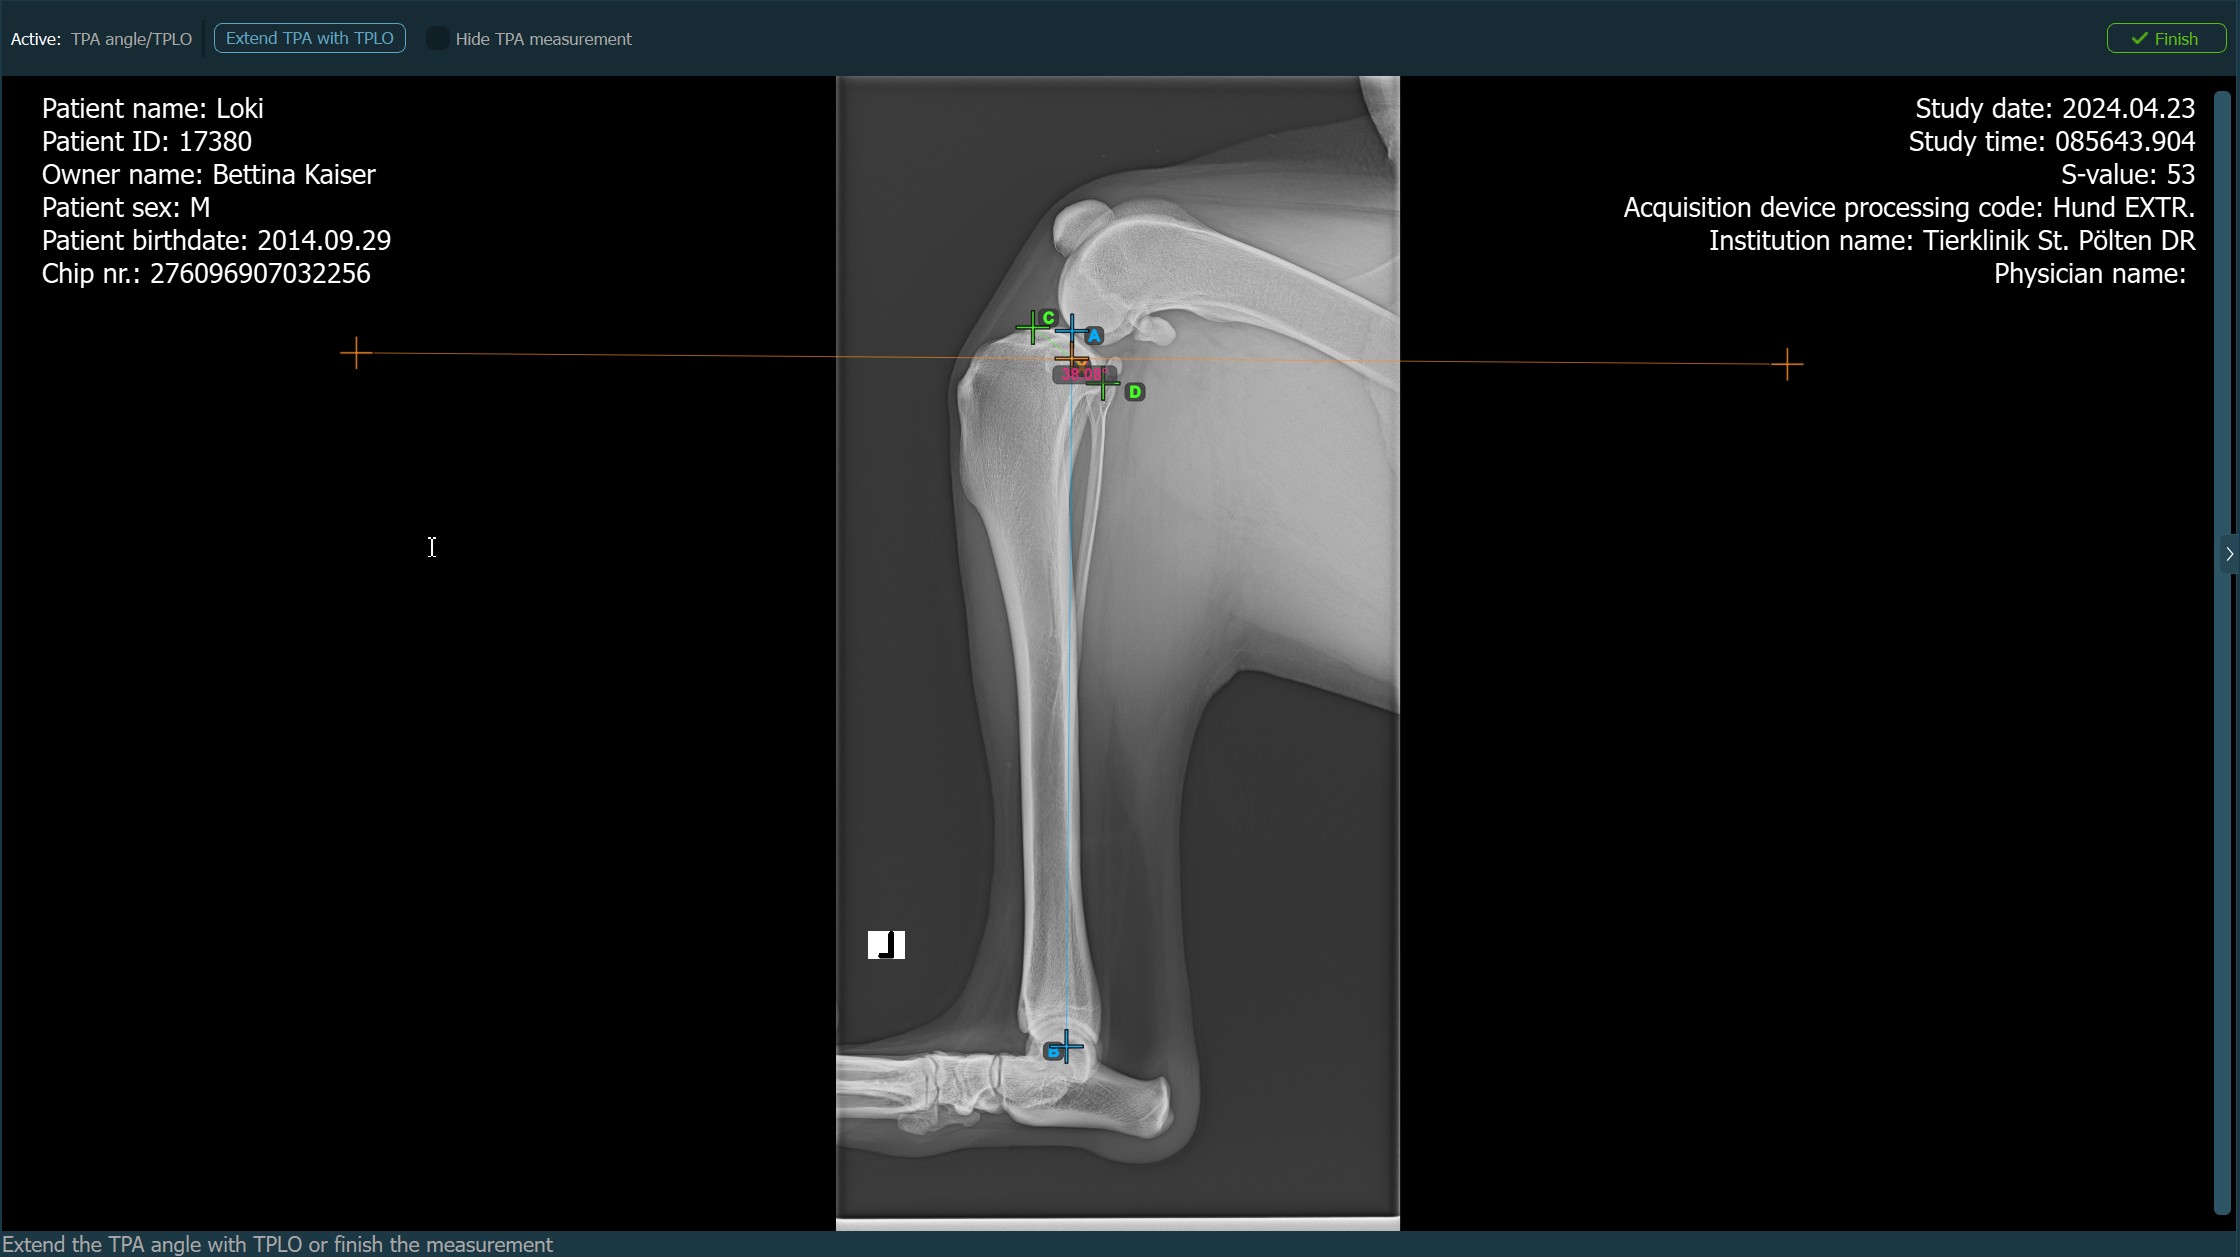

Ha a TPLO kiterjesztés engedélyezve van a TPA szög méréséhez, válassza ki az elérhető lehetőségek egyikét a komplex mérésmód eszköztárából a mérés folytatásához/befejezéséhez. Ellenkező esetben a TPA szög mérés automatikusan befejeződik.

Nyomja meg a

Befejezésgombot a TPA szög mérésének megerősítéséhez és befejezéséhez TPLO kiterjesztés nélkül.Aktiválja a TPLO kiterjesztést a

TPA TPLO-val történő kiterjesztésegomb használatával.A TPA szög mérés elrejtéséhez vagy megjelenítéséhez a TPLO kiterjesztés során jelölje be vagy törölje a jelölést a

TPA mérés elrejtésejelölőnégyzetben.![]()